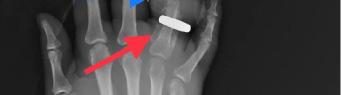

CPC-EM Capsule

What do we already know about this clinical entity?

Porphyria attacks cause a high degree of morbidity but are under-recognized in emergency departments secondary to lack of understanding of the diseases and their associated confirmatory tests.

What makes this presentation of disease reportable?